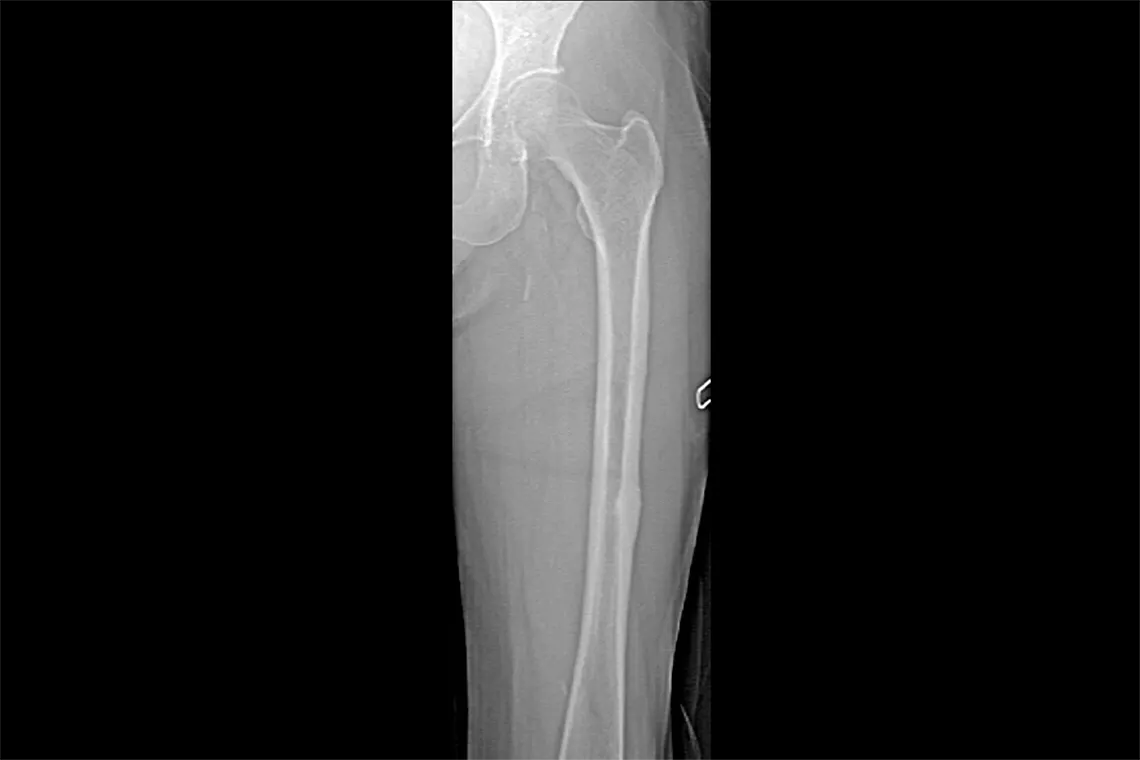

Horizon DXA produces radiographic quality images of the entire femur for assessment of potential atypical femur fractures.31 A quick, 15-second scan reveals cortical thickening of the bone, making it fast and easy to monitor the effects of bisphosphonate therapy over time.

Visualise calcified plaque in the abdominal aorta, which may be a significant indication of heart disease and stroke, two of the leading causes of death in men and women.